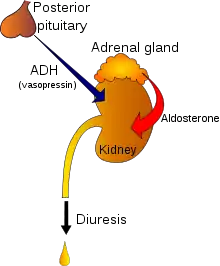

| Regulation of urine production by ADH and aldosterone | |

The most common cause of polyuria in both adults and children is uncontrolled diabetes mellitus,[6] which causes osmotic diuresis, when glucose levels are so high that glucose is excreted in the urine. Water follows the glucose concentration passively, leading to abnormally high urine output. In the absence of diabetes mellitus, the most common causes are decreased secretion of aldosterone due to adrenal cortical tumor, primary polydipsia (excessive fluid drinking), central diabetes insipidus and nephrogenic diabetes insipidus.[6] Polyuria may also be due to various chemical substances, such as diuretics, caffeine, and ethanol. It may also occur after supraventricular tachycardias, during an onset of atrial fibrillation, childbirth, and the removal of an obstruction within the urinary tract. Diuresis is controlled by antidiuretics such as vasopressin, angiotensin II and aldosterone. Cold diuresis is the occurrence of increased urine production on exposure to cold, which also partially explains immersion diuresis. High-altitude diuresis occurs at altitudes above 10,000 feet (3,000 m) and is a desirable indicator of adaptation to high altitudes. Mountaineers who are adapting well to high altitudes experience this type of diuresis. Persons who produce less urine even in the presence of adequate fluid intake are probably not adapting well to altitude.